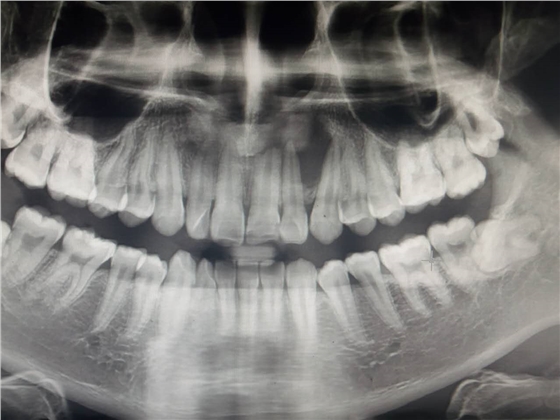

死髓牙2度,沒保留價值了,外傷造成的外吸收,即使到充也容易出問題。和患者溝通,要求做種植,用了兩個骨膠原,側切、尖牙沒事,側切做了一次根充